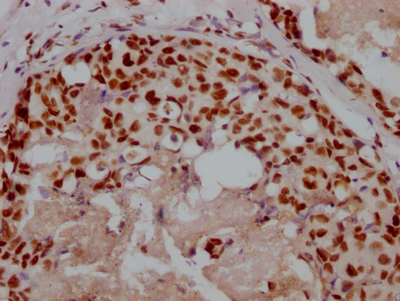

Immunohistochemistry of paraffin-embedded human testis tissue using CSB-PA525314HA01HU at dilution of 1:100